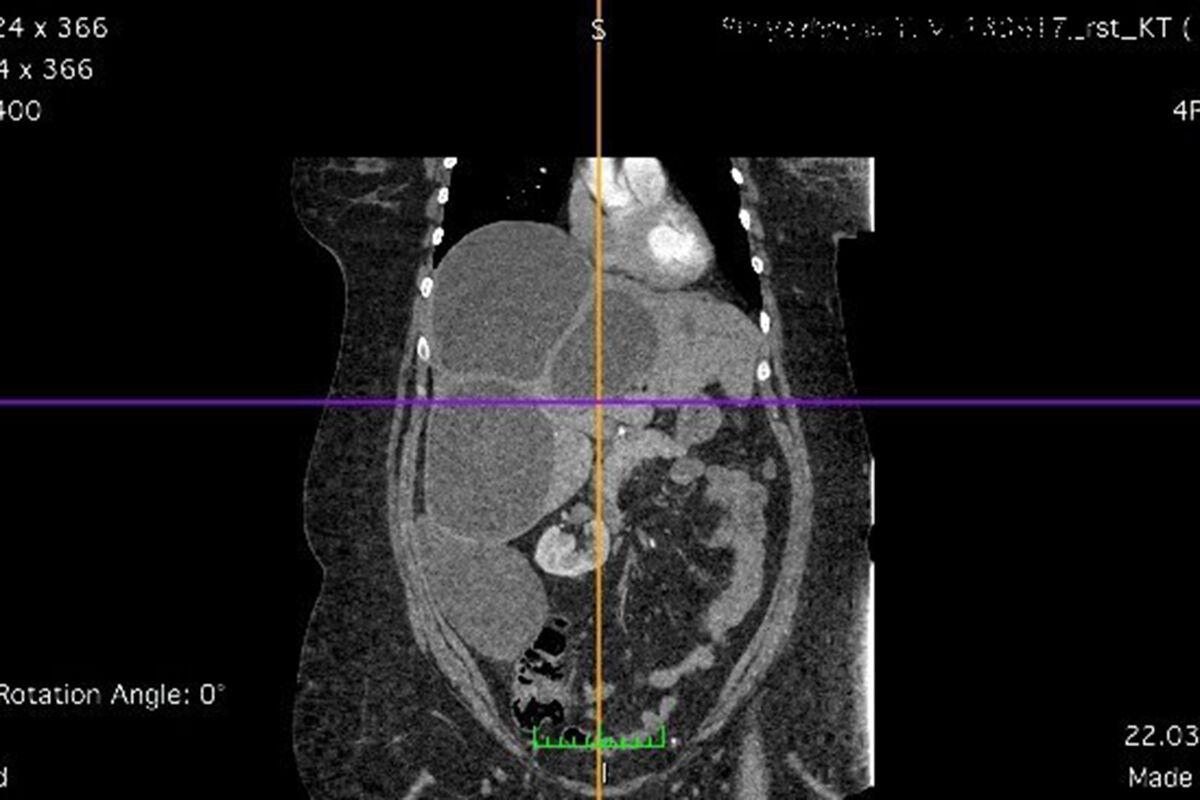

«У пациентки при проведении спиральной компьютерной томографии обнаружен значительный объем поражения печени эхинококкозом — практически всей правой и части левой доли. Четыре крупных эхинококковых кисты заместили более 50 процентов ткани печени», — рассказал заведующий кафедрой оперативной хирургии и топографической анатомии университета Юрий Хоронько.